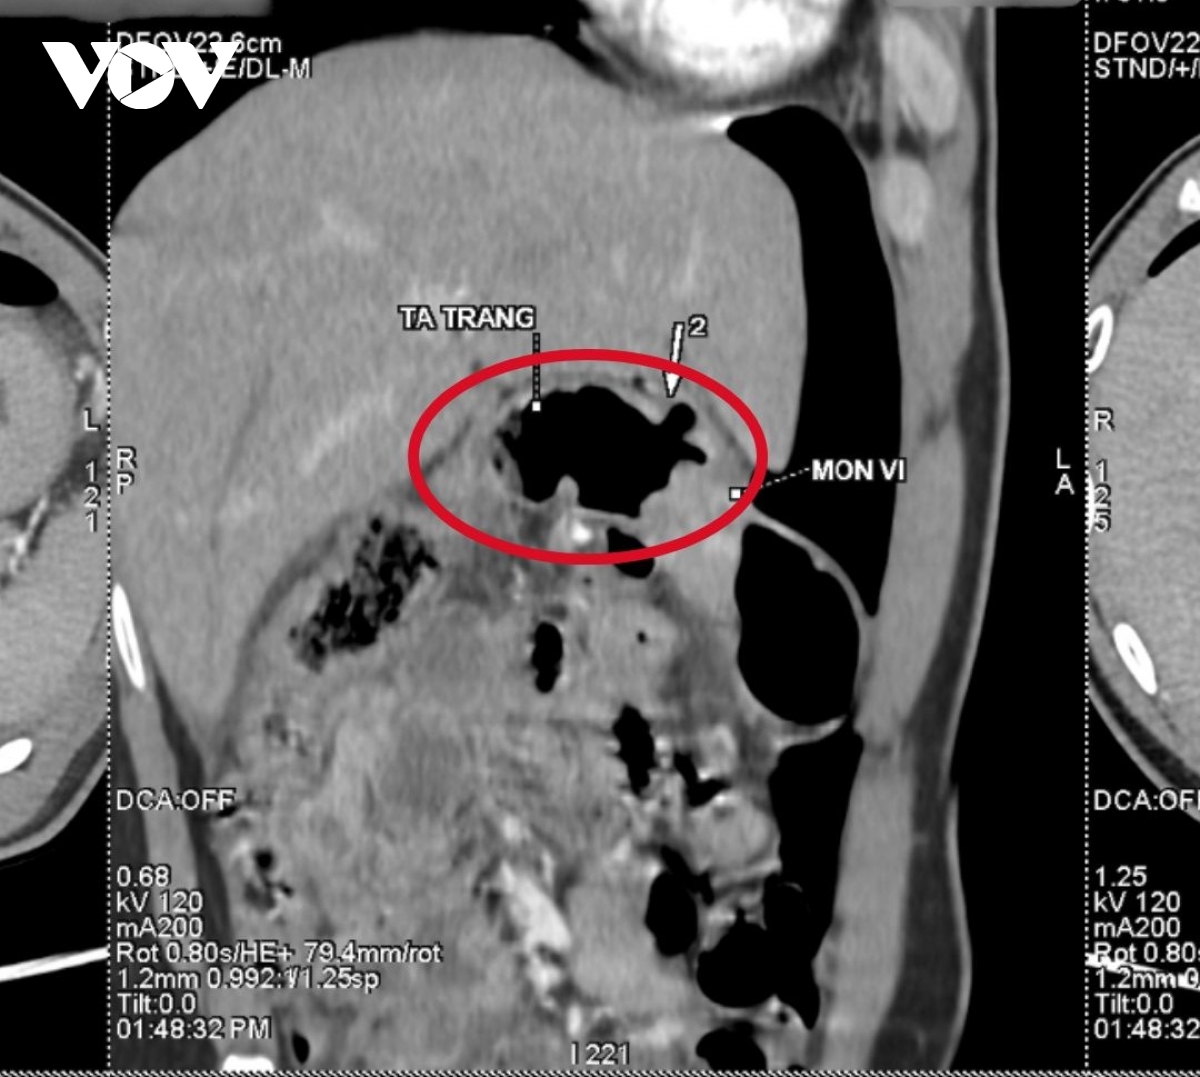

Qua thăm khám, kết quả chụp CT ghi nhận thủng vị trí mặt trước hành tá tràng, kèm dịch, khí tự do trong ổ bụng và thâm nhiễm mỡ, nguyên nhân ban đầu được xác định liên quan đến ổ viêm loét dạ dày, tá tràng tồn tại từ trước nhưng chưa được phát hiện, điều trị triệt để.